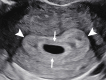

The Society of Radiologists in Ultrasound convened a multisociety panel to develop a first-trimester US lexicon based on scientific evidence, societal guidelines, and expert consensus that would be appropriate for imagers, clinicians, and patients. Through a modified Delphi process with consensus of at least 80%, agreement was reached for preferred terms, synonyms, and terms to avoid. An intrauterine pregnancy (IUP) is defined as a pregnancy implanted in a normal location within the uterus. In contrast, an ectopic pregnancy (EP) is any pregnancy implanted in an abnormal location, whether extrauterine or intrauterine, thus categorizing cesarean scar implantations as EPs. The term pregnancy of unknown location is used in the setting of a pregnant patient without evidence of a definite or probable IUP or EP at transvaginal US. Since cardiac development is a gradual process and cardiac chambers are not fully formed in the first trimester, the term cardiac activity is recommended in lieu of 'heart motion' or 'heartbeat.' The terms 'living' and 'viable' should also be avoided in the first trimester. 'Pregnancy failure' is replaced by early pregnancy loss (EPL). When paired with various modifiers, EPL is used to describe a pregnancy in the first trimester that may or will not progress, is in the process of expulsion, or has either incompletely or completely passed. © RSNA and Elsevier, 2024 Supplemental material is available for this article. This article is a simultaneous joint publication in Radiology and American Journal of Obstetrics & Gynecology. All rights reserved. The articles are identical except for minor stylistic and spelling differences in keeping with each journal's style. Either version may be used in citing this article. See also the editorial by Scoutt and Norton in this issue.